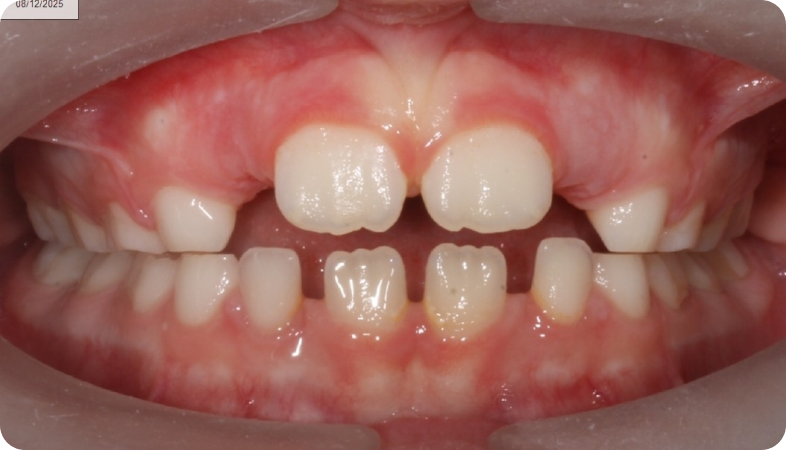

Cas cliniques